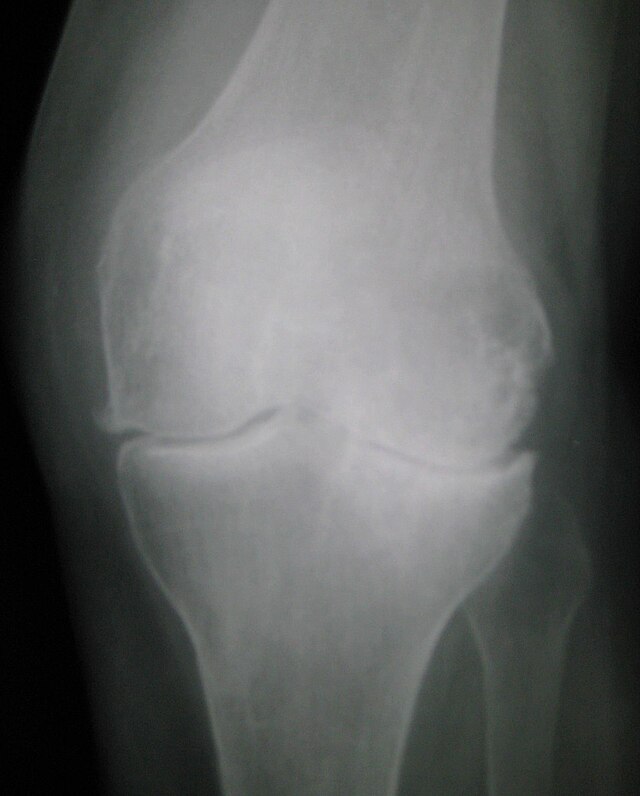

Artroz

13

0